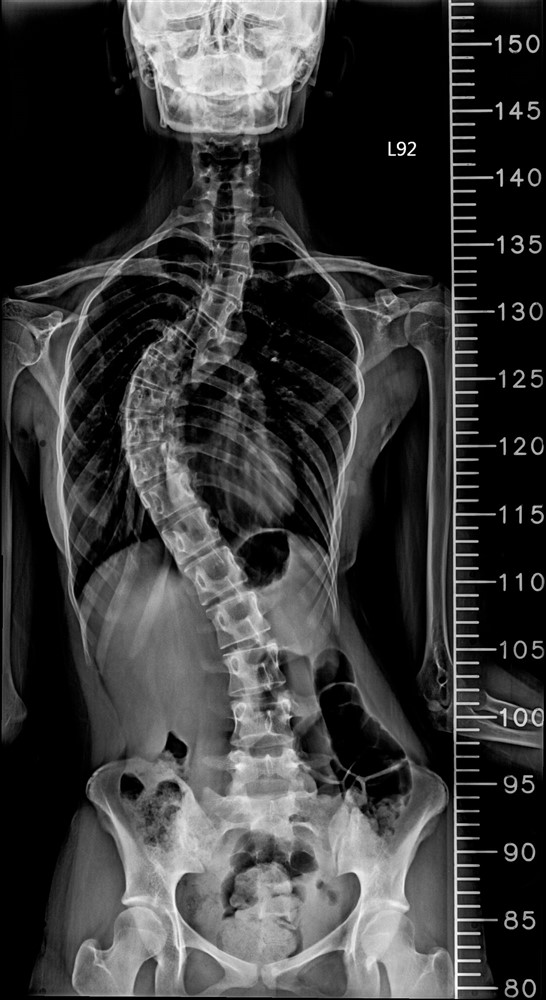

少女脊椎側彎手術:

精準導航改變手術風險

十七歲的何同學在國中時期便被父母注意到體態問題,確診為脊椎側彎。當時因角度尚未惡化,家人僅持續追蹤觀察。但隨著成長,側彎角度逐漸加重,影響了少女最在意的身形外觀,何同學及父母跟醫師討論評估後,醫師建議進行矯正手術。台中慈濟醫院神經醫學中心主任林英超表示,青少年的長節脊椎側彎矯正一直被視為高難度手術,不僅手術時間長,也可能伴隨出血量大與神經損傷風險。因此,神經醫學中心團隊安排在「複合式手術室」進行手術。

醫療團隊在何同學的手術中,運用三維立體導航系統與複合手術室影像設備,即時建立脊椎三維影像。醫師可以在螢幕上清楚看到每一節椎骨與椎弓根的角度,並計算最佳螺釘植入路徑。透過導航系統輔助,鈦合金骨釘的置放精準度提升到接近百分之百,大幅降低神經傷害與植體偏移風險。

手術後的復原速度也明顯加快。何同學術後第三天便能下床活動,一星期左右疼痛明顯減輕。她表示,手術後身體姿勢變得更挺直,走路、彎腰等日常生活都逐漸恢復正常。在過去傳統手術,要達到這樣的復原速度,往往需要好幾個月才能達到。

台中慈濟醫院神經醫學中心於複合式手術室成功完成脊椎側彎矯正,術後復原速度較傳統快速許多。